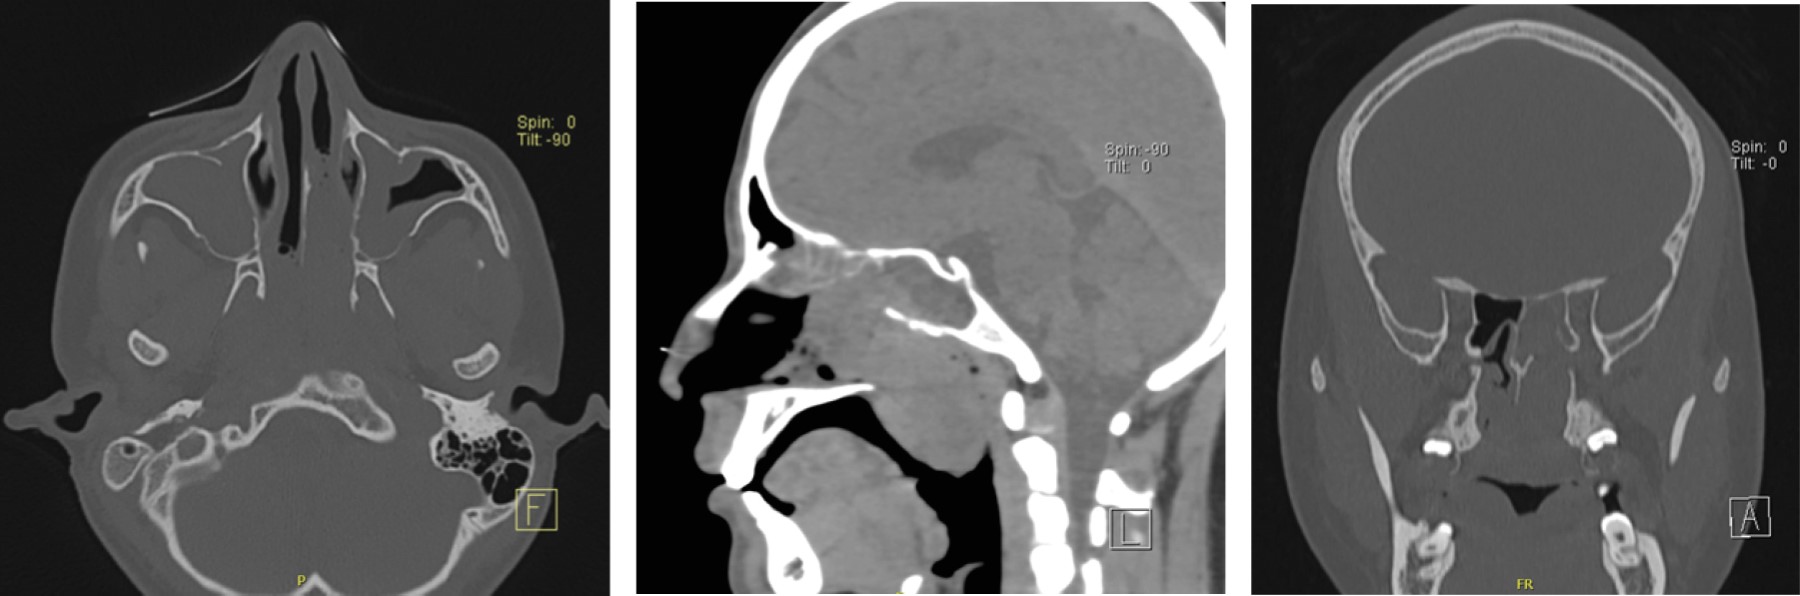

En TC se observa lesión isodensa con respecto al músculo que realza de manera heterogénea al medio de contraste; ocupa fosa pterigopalatina izquierda y desciende hacia nasofaringe, abarca el 100% de la luz de coana izquierda, extendiéndose hacia el área IV de Cottle con erosión del seno esfenoidal; también se observa extensión de dicha lesión a orofaringe, la cual condiciona desplazamiento del paladar blando (Figura 3).

Figura 4